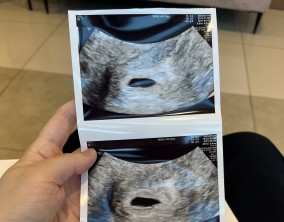

설렘과 불안의 시간을 지나 찾아온 선물

서울IVF여성의원의 난임 치료는 과정 하나하나가 체계적이고 세심하다는 인상을 받았습니다. 이유정 원장님과 간호사 분들께 치료 단계마다 충분한 설명을 들을 수 있어 불안이 많…